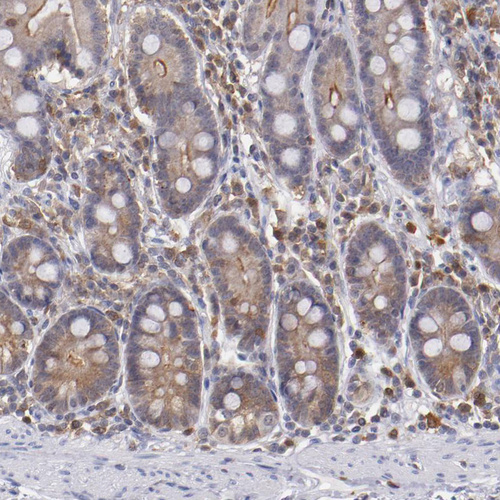

Immunohistochemistry analysis in human tonsil and skeletal muscle tissues using HPA001890 antibody. Corresponding PRKCD RNA-seq data are presented for the same tissues.